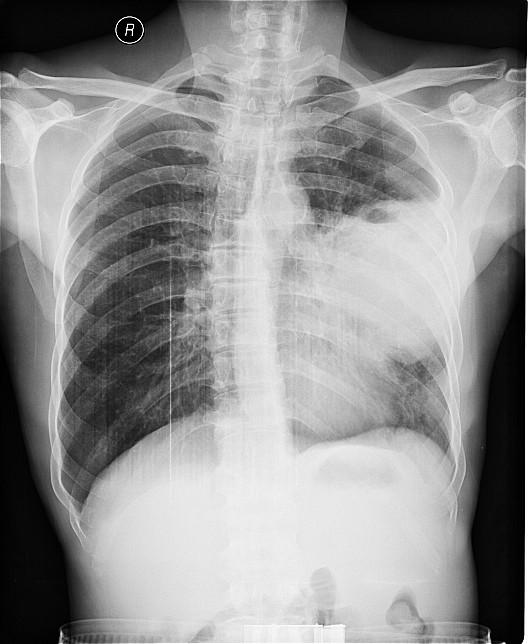

标题: X3612:男,48岁,咳嗽气逼月余 [打印本页]

标题: X3612:男,48岁,咳嗽气逼月余

实性包块,上有小液平,如无脓肿症状,考虑肺癌

肺脓肿应该是边缘不清楚吧,而这个好象是块状密度增高影,所以我觉得是周围性肺癌引起的空洞.